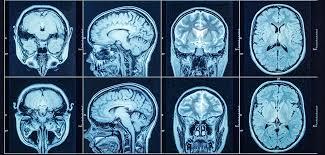

A CT (Computed Tomography) scan is a medical imaging procedure that combines X-ray measurements with computer technology to create detailed cross-sectional images of the body. Unlike regular X-rays, CT scans provide more comprehensive views of bones, organs, tissues, and blood vessels.

During the procedure, the patient lies on a motorized table that slides into a circular scanner. The machine rotates around the body, capturing multiple images from different angles. These images are then processed by a computer to create detailed 3D visuals.

1. Head and Brain CT Scan

Used to detect strokes, tumors, and head injuries.

3. Detailed Imaging

Offers high-resolution images for better evaluation.